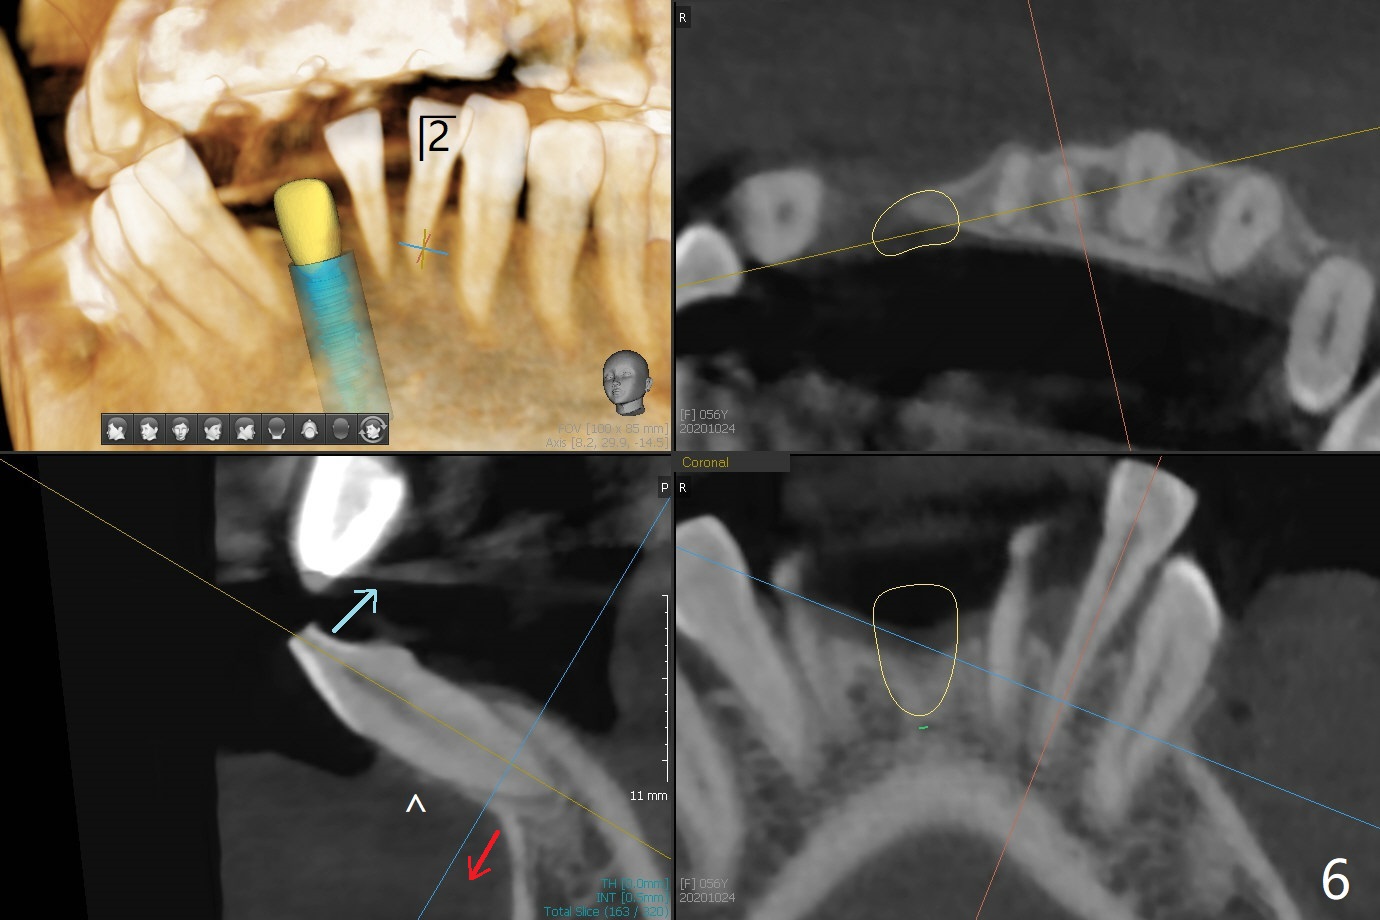

56岁女牙周炎,失去右上6,7以及右下1,后者缺牙间隙特别宽,其余切牙往颊侧移位(flare,病人不愿意拔除,图一)。右上植牙修复后(图二,三),下前牙种植(图四,五(选择窄植体)),建立正常覆盖,同时在邻近切牙唇侧植骨(图七,八:红线)。四-六个月后做局部矫正:使用植牙作为支抗将颊侧移位的前牙(牙冠)往舌侧推移(图七,八:蓝箭头),而牙根可能往唇侧移位(图六:红箭头),所以事先植骨(图七,八:红线)重要。矫正后3-3舌侧放置钢丝树脂固定。Jennifer: #25 implant and crown should be lingualized, as compared to the rest of the lower incisors (flared). After osteointegration, ortho will be conducted to correct the flaring using #25 implant as an anchor.